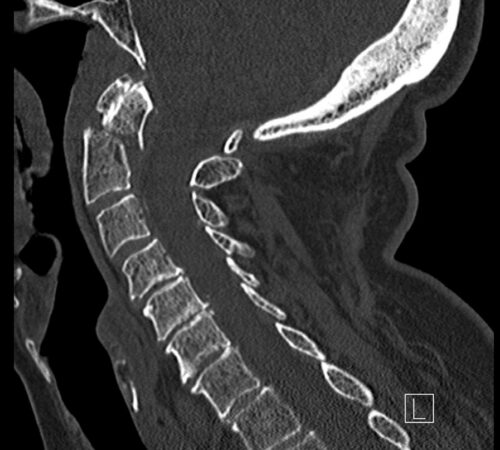

CT

CT (počítačová tomografie) je skvělé na zobrazení kostí a přesné určení, kde je zlomenina a o jaký typ se jedná.

U pacientů s více zraněními (polytrauma) se RTG často přeskakuje a rovnou se dělá CT (celé páteře, protože je to rychlejší a detailnější. Pokud je poranění méně závažné, CT se zaměřuje jen na postiženou oblast, přičemž se prohlédne alespoň tři obratle nad a pod místem zranění.

Jestliže po úrazu se manifestují neurologické potíže, jako je brnění, slabost nebo ztráta citlivosti, doplňuje se magnetická rezonance (MR), která detailně zobrazí měkké tkáně a zmapuje vnitřek páteřního kanálu. U dětí se MR dělá hned jako druhé vyšetření a CT až dle toho, co MR odhalí, aby se minimalizovala radiační zátěž.